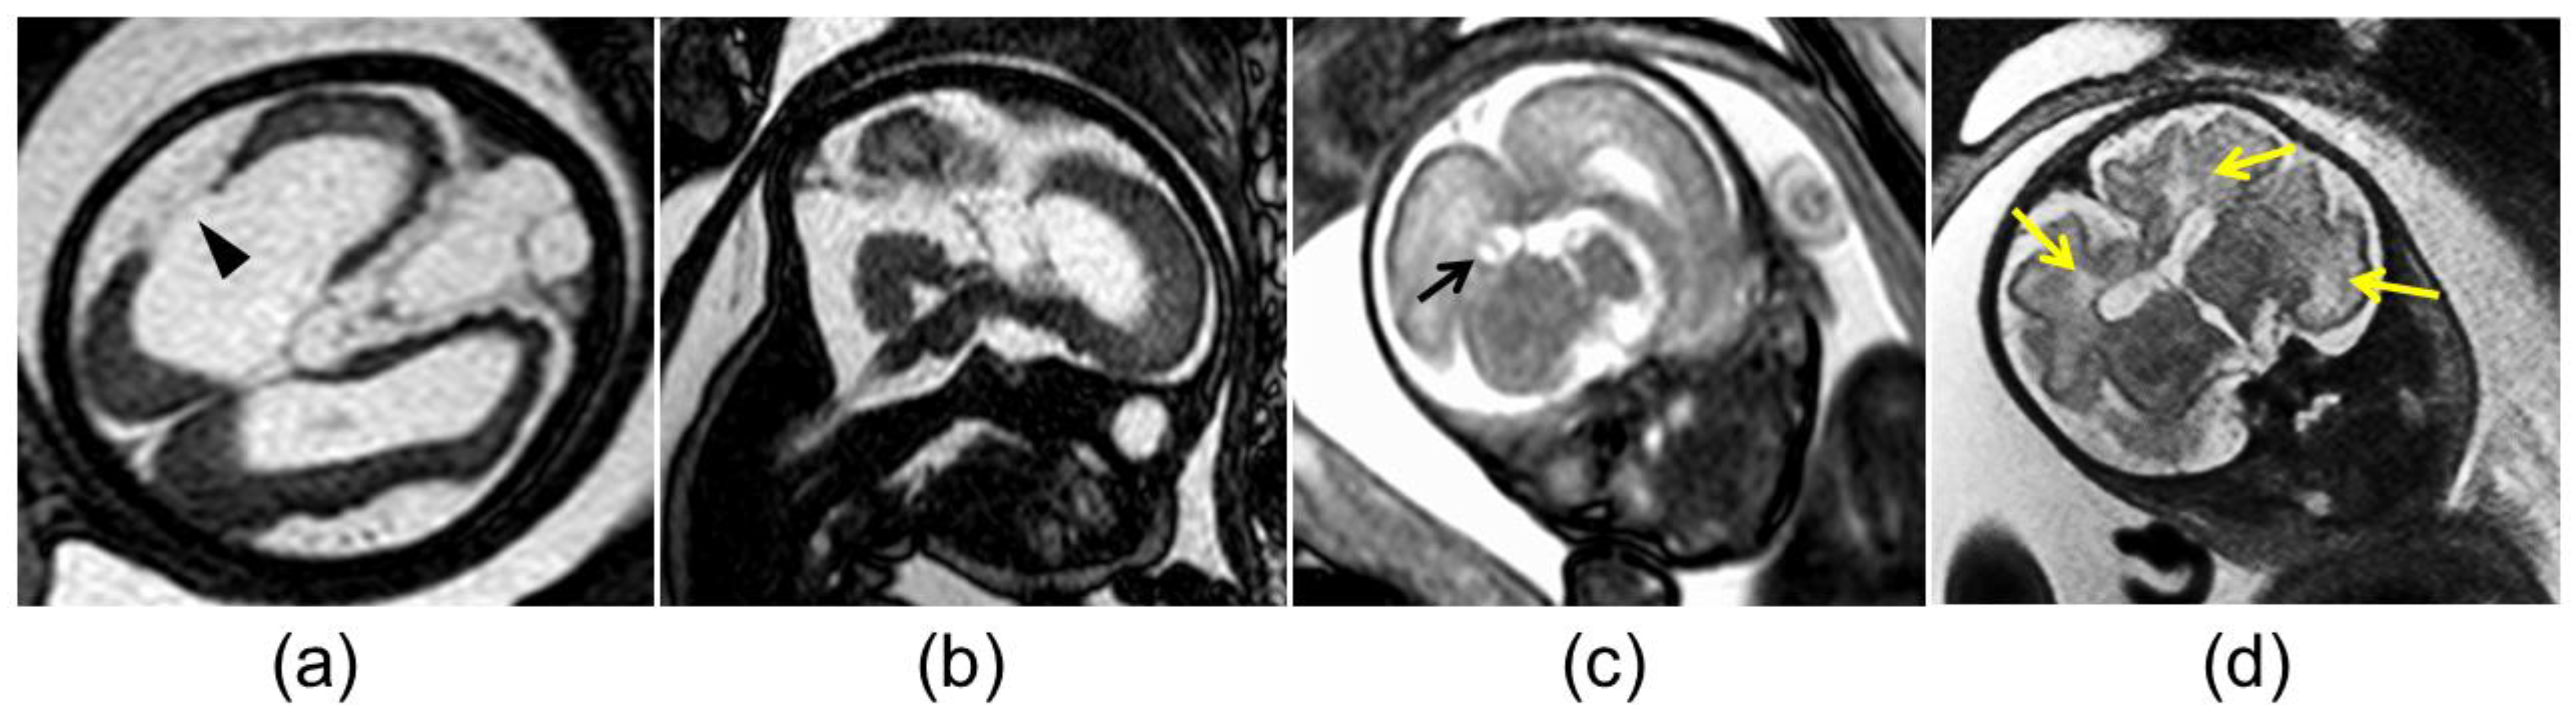

The mothers of the 18 fetuses underwent magnetic resonance imaging (MRI) examinations using a 1.5T MR system (Gyroscan NT, Philips, Best, The Netherlands). The MRI protocol included axial, sagittal, and coronal T2 weighted images (T2WI) using half-Fourier acquisition single-shot turbo spin-echo, balanced fast-field echo imaging, and axial double-echo gradient-echo chemical shift imaging. Two board-certified radiologists with more than 10 years’ experience (H.H. and Y.U.) retrospectively evaluated the MR images for the following findings: ventriculomegaly, pseudocysts, cortical malformation, cerebellar hypoplasia, and white matter (WM) hyperintensity on T2WI (Figure 2). The two radiologists independently evaluated the MR images, and the final diagnoses were made by consensus. During the interpretation, the radiologists were aware that the fetuses had cCMV but were blind to information about fetal US, as well as neonatal clinical findings and outcomes.

Figure 2. Abnormal magnetic resonance imaging findings in the brain of fetuses with congenital cytomegalovirus infection: (a) cortical malformation and schizencephaly (arrowhead); (b) vermian hypoplasia; (c) atrium pseudocyst (black arrow); (d) white matter hyperintensity (yellow arrows).